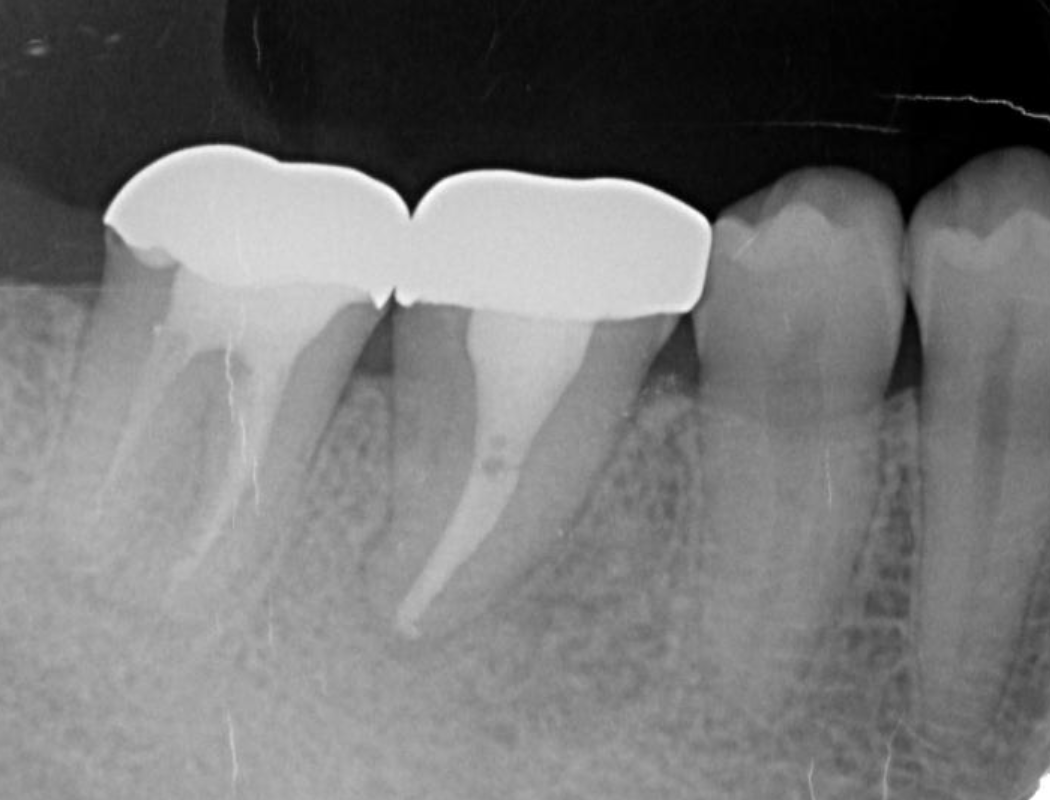

Bone regeneration was confirmed before and after grafting, after root filling, and after placement of the prosthesis, based on X-ray imaging results (Figure 8). There was no pathologic mobility or pain during mastication, and the tooth showed good function. The patient was very satisfied with the treatment results (Figure 9).

Figure 8.Cone beam CT image obtained after transplantation. Bone regeneration around the grafted tooth was confirmed.

Figure 9.Dental X-ray image obtained two years after transplantation. Bone regeneration around the grafted tooth was confirmed.